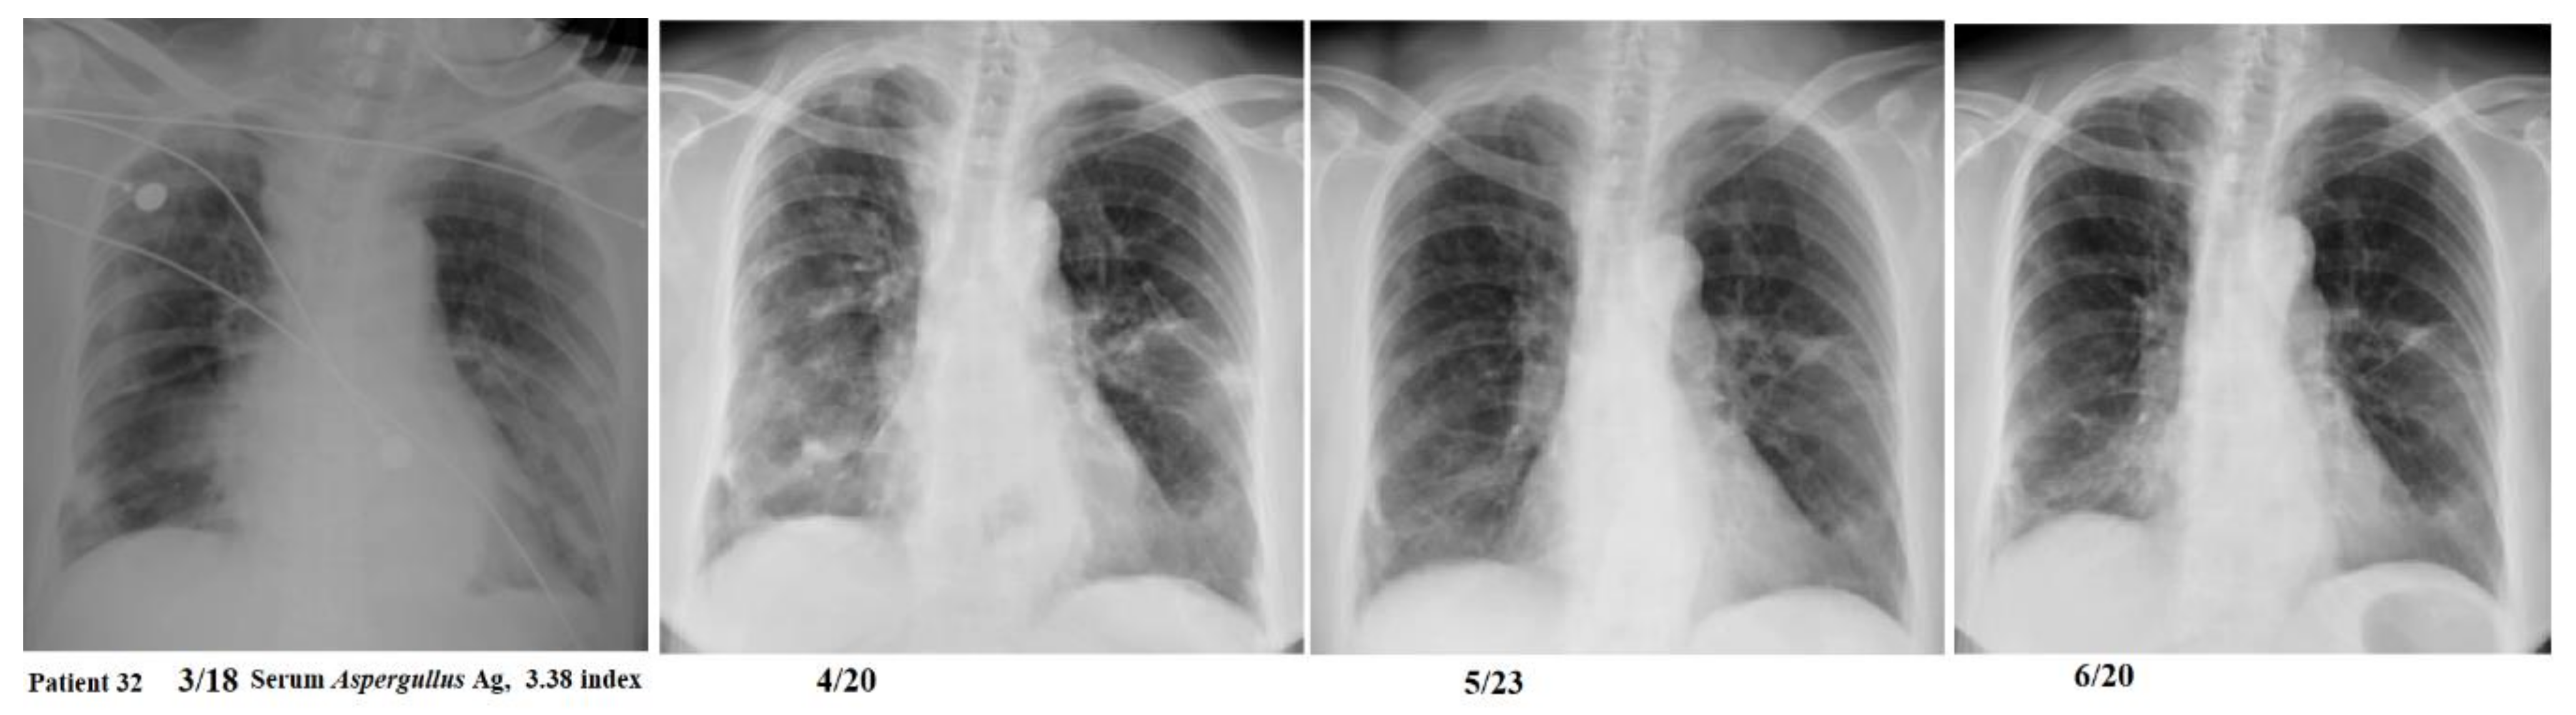

| Patient 32 | 64 F | nil | moderate | 141.6 | 2 | 0 | survived | 20 | 3.38 | NA |